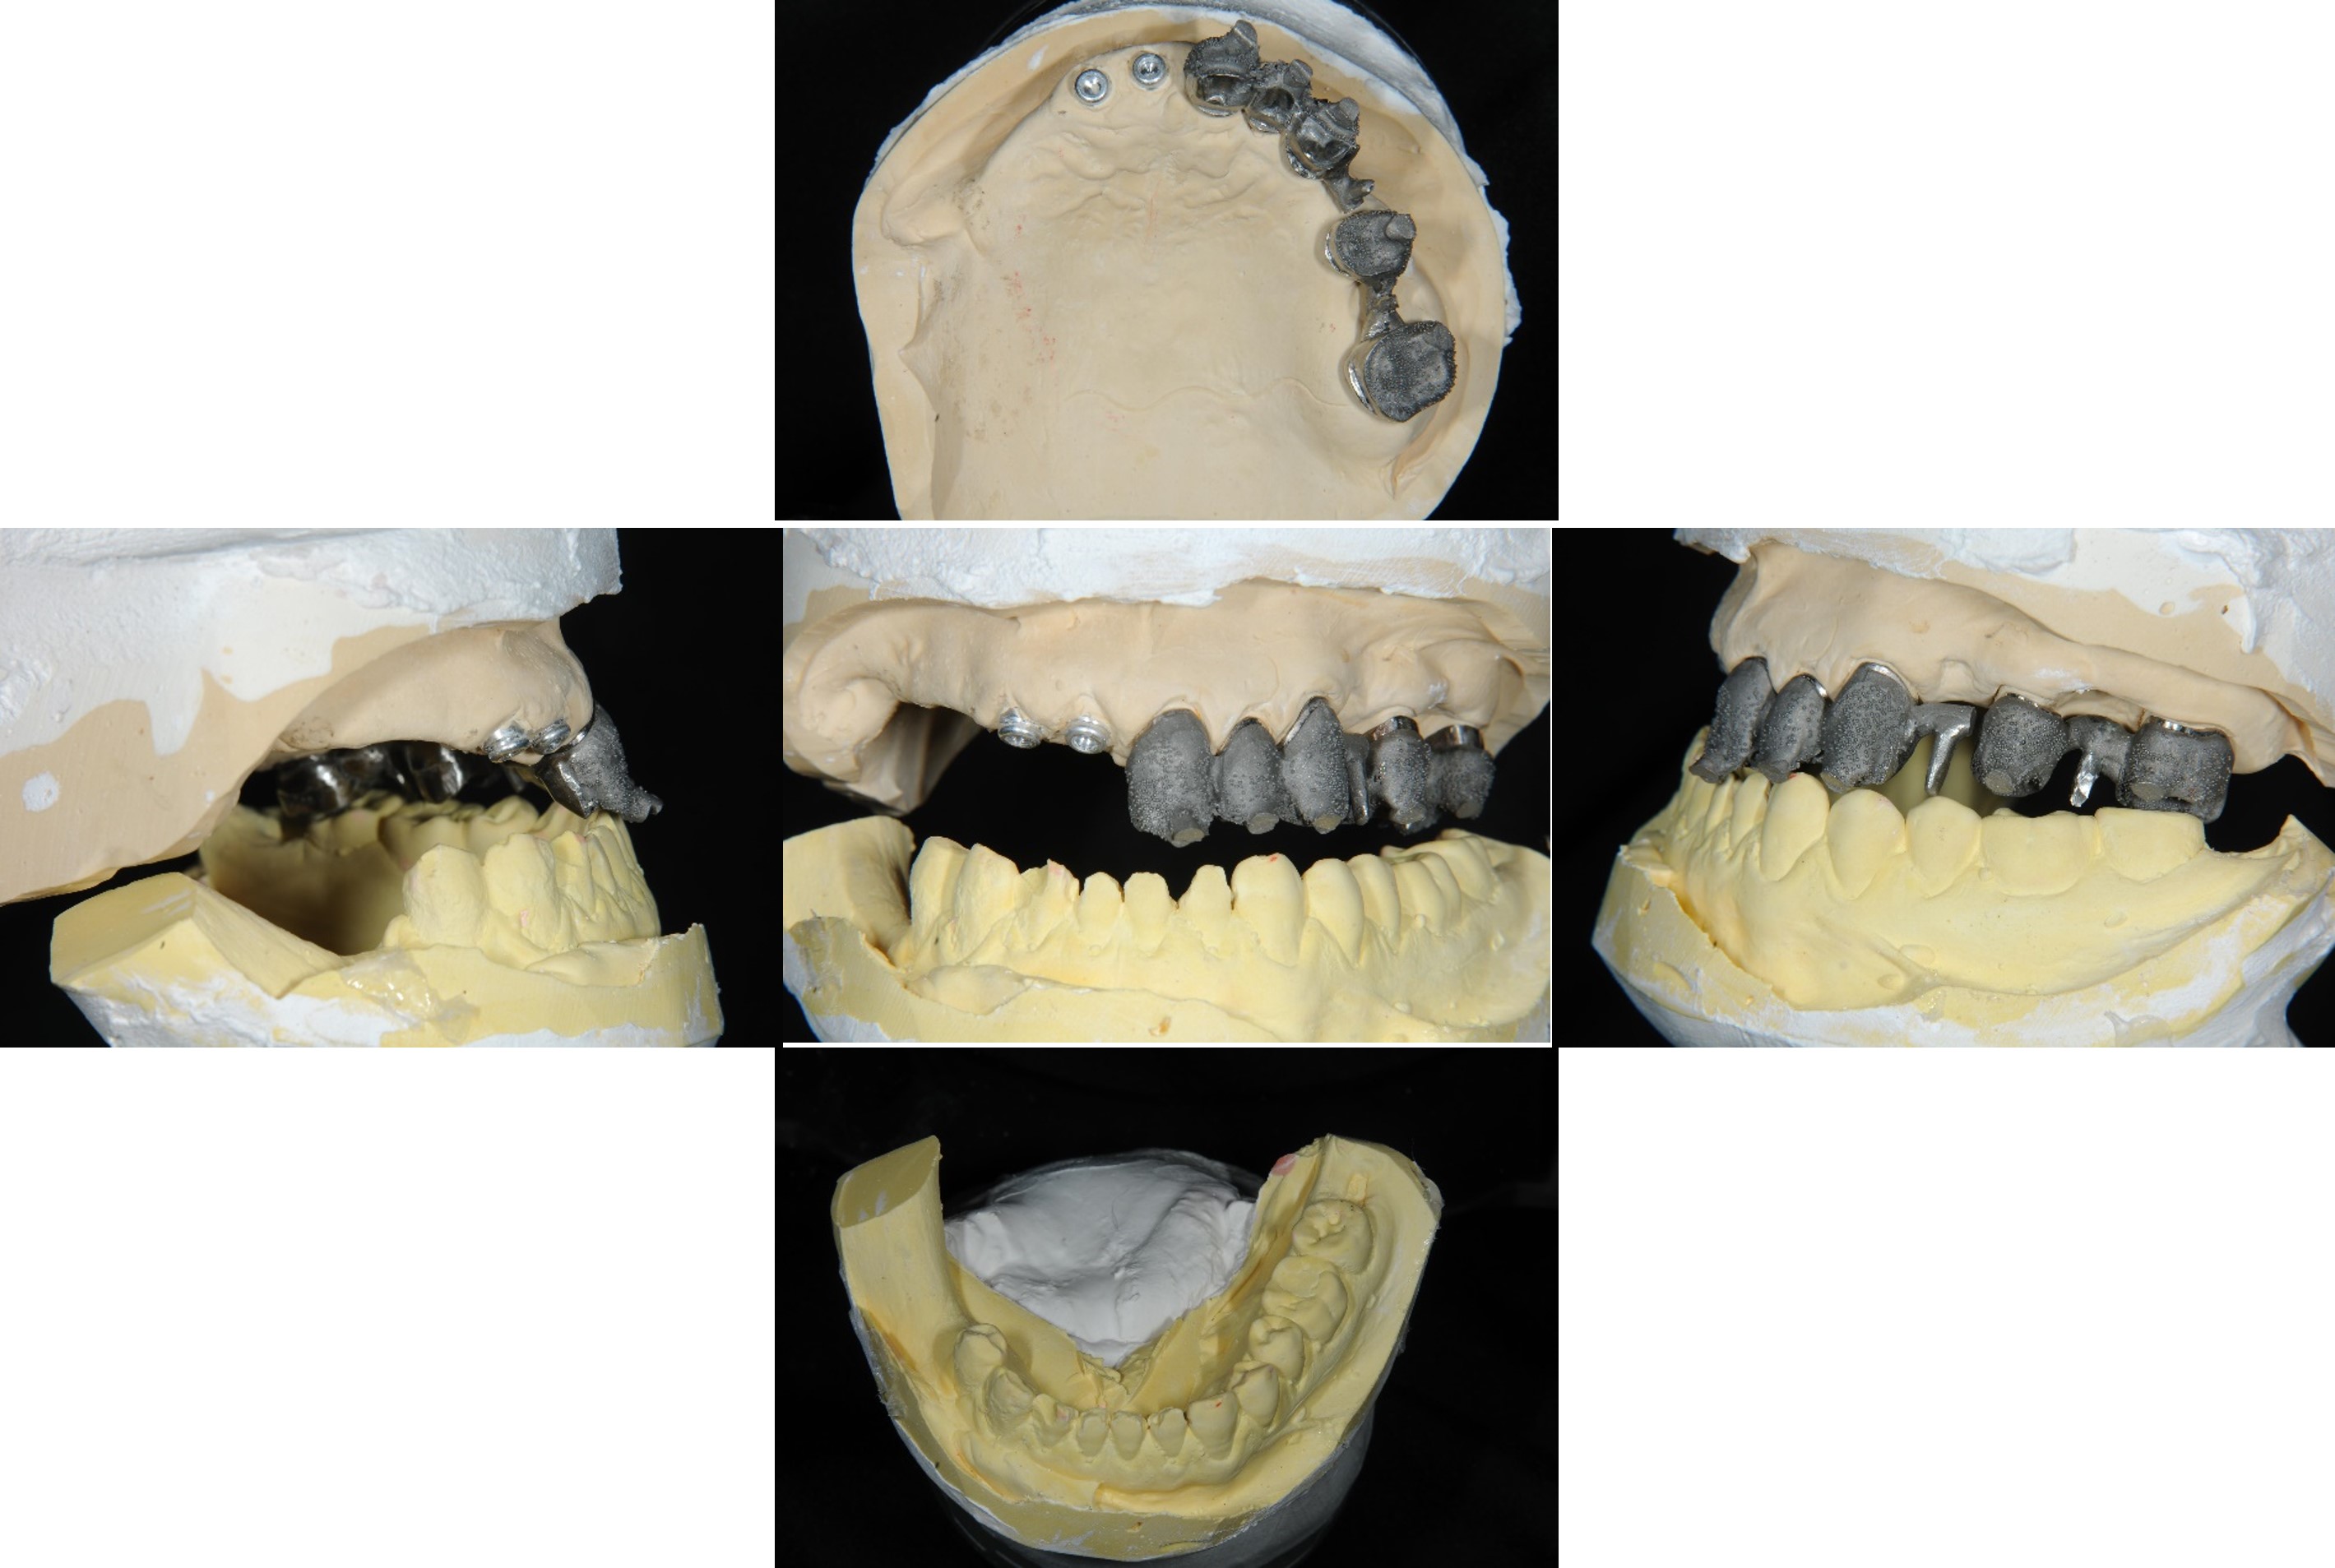

上顎支柱牙

內外冠及活動假牙

內冠套件

內外冠支撐活動假牙